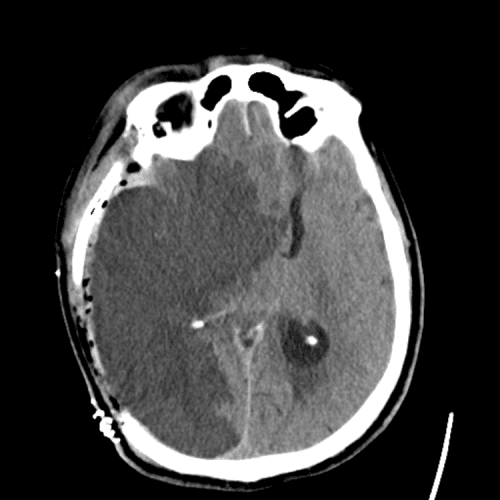

PICA infarct

PCA infarct